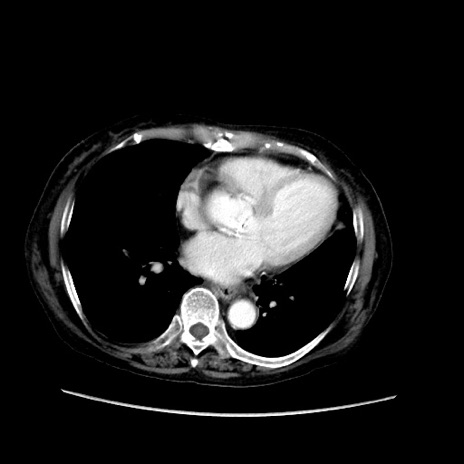

症例31(横断像)

【症例】80歳代 女性

【主訴】腹部膨満感

【現病歴】他院にて肝硬変にてフォロー中。1週間前から便秘、腹部膨満感、臍部腫瘤あり受診となる。

【既往歴】肝硬変

【身体所見】腹部膨隆あり、皮膚変化なし、疼痛なし。

【データ】WBC 4600、CRP 0.25